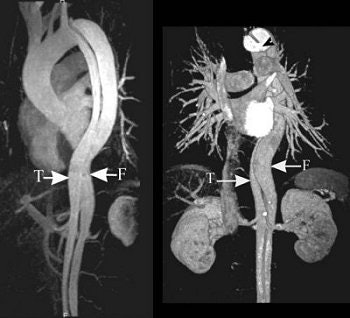

The series of images illustrate the typical manifestations of aortic dissection, including Stanford A (top image, both VR; second image, axial MPR) and Stanford B (third image, arterial phase VR, venous phase VR; fourth image, MIP and VR; fifth image, axial MPR). T = true lumen. F = false lumen. Black arrowhead = entry site. All images courtesy of Qi Liu, Ph.D.